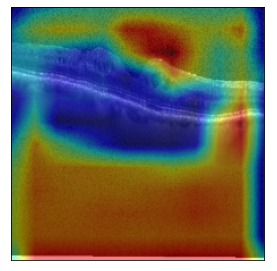

Using Grad-CAM we further explore the interpretability to offer important information to medical practitioners.

GradCAM

GradCAM

GradCAM

GradCAM

Fig 6, 7, 8 and 9 depicts the visualization of correct predictions by our proposed CNN model where fig 6 is class CNV, fig 8 is class DME, fig 7 is DRUSEN and finally, fig 9 is NORMAL. Here the first photo in every class is the original image. The LIME map of our suggested model’s prediction is shown in image B whereas in image C the positive region is highlighted in specific sections on the original image. For Image D we have increased the number of features from 5 to 10 thus more regions have been predicted as the positive region which is highlighted in green. After increasing the features from 5 to 10, some of the regions are predicted wrongly. The red regions represent the output of incorrect prediction. The following image represents the Grad-CAM heatmap highlighting the regions with our model’s prediction.